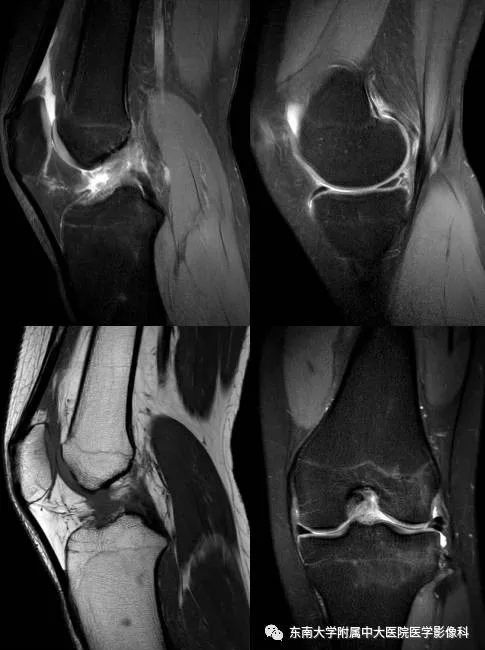

前交叉韧带损伤1例MR影像诊断

女,16岁,因“外伤致左膝疼痛伴活动受限2月余”入院。

病例结果:前交叉韧带损伤